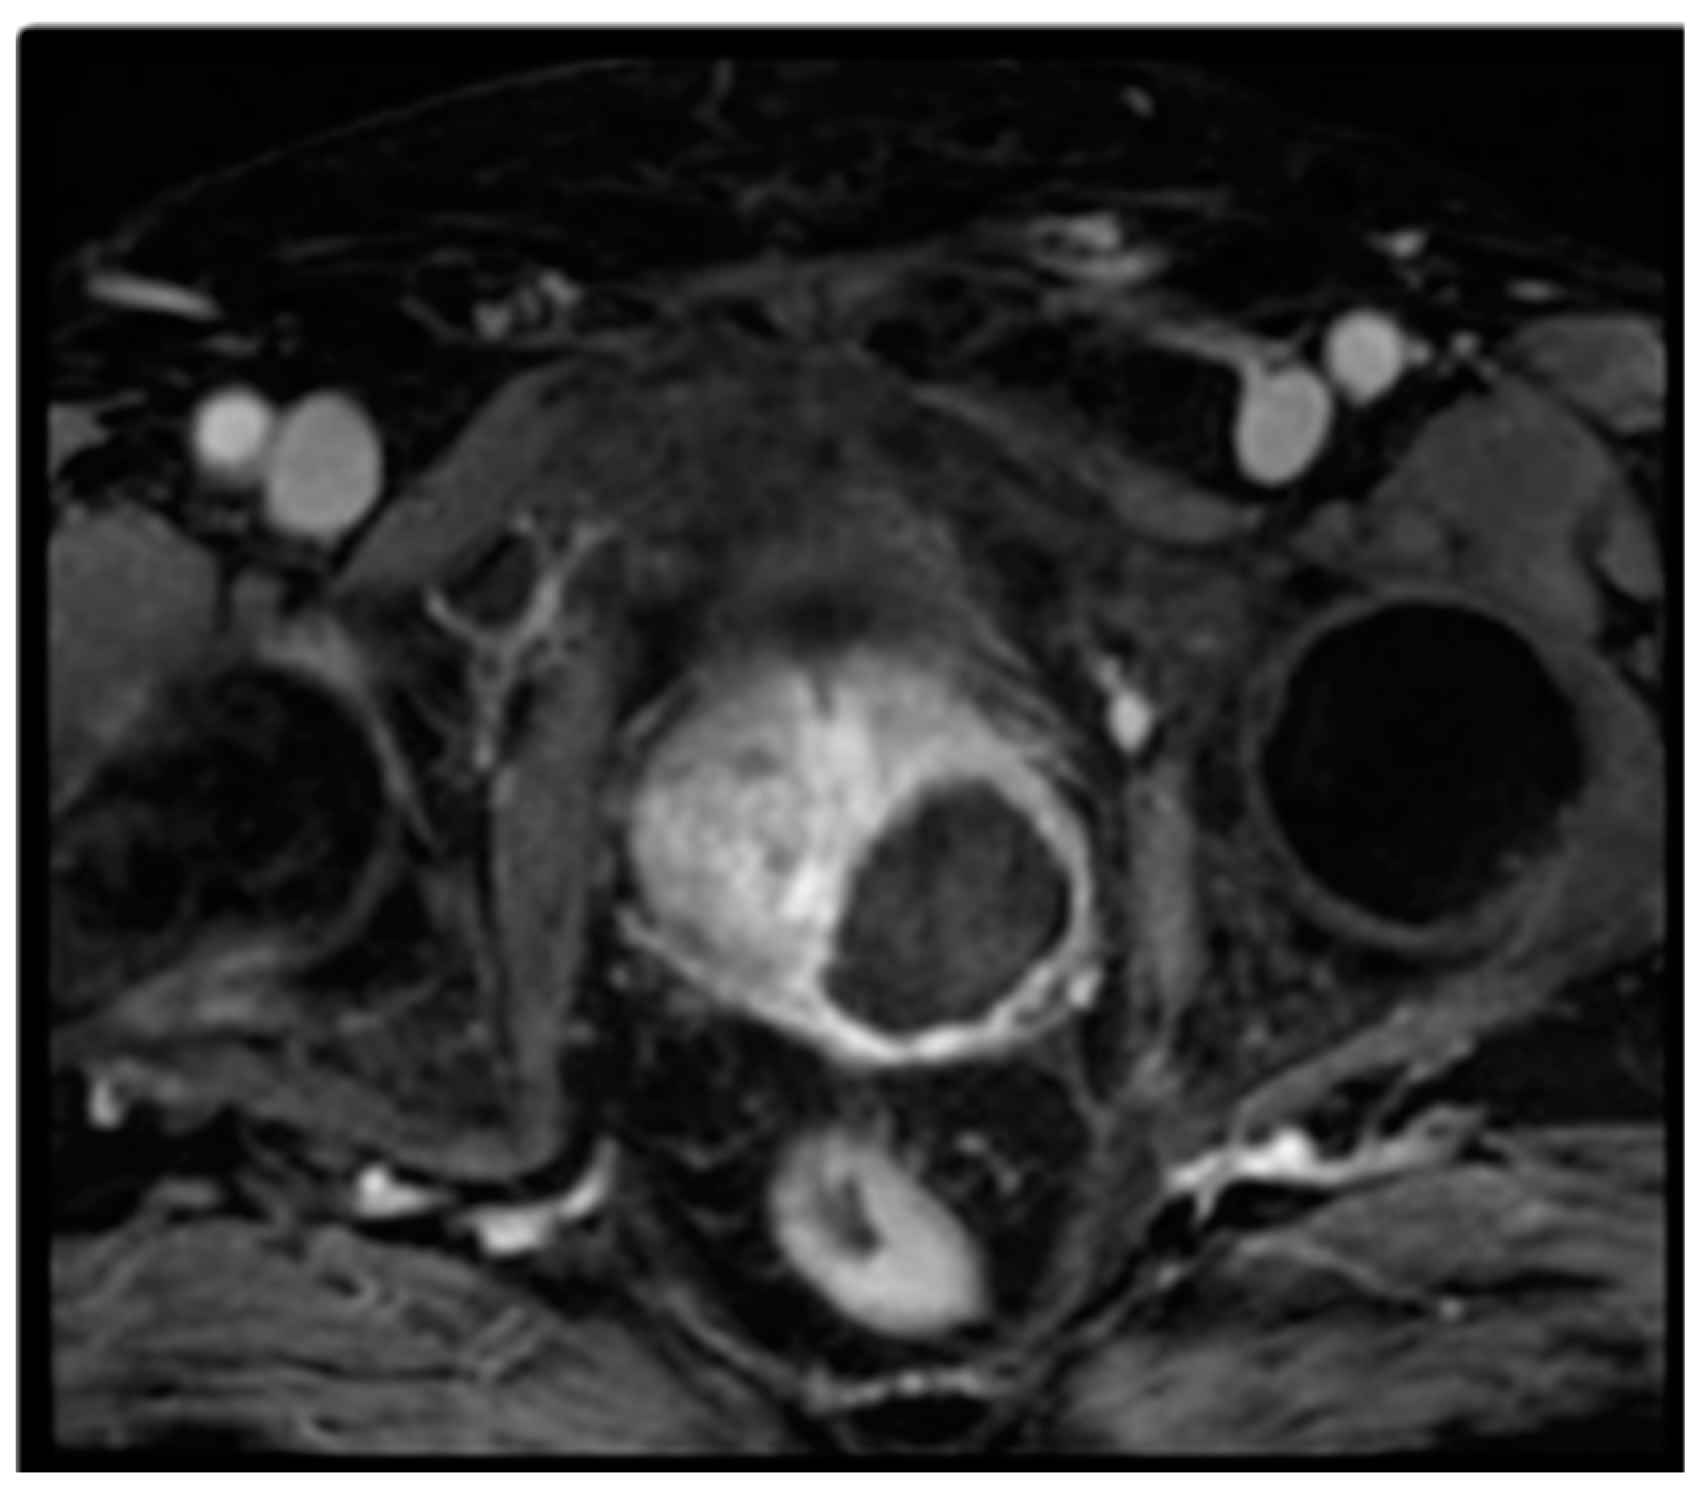

Abstract

2. Materials and Methods

2.1. Padeliporfin VTP Procedure